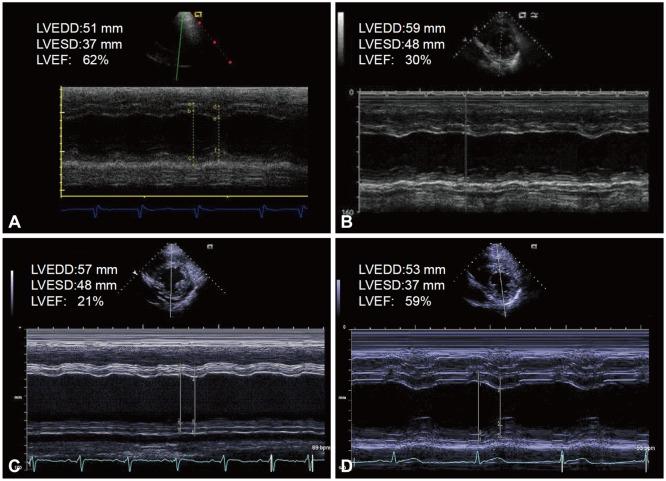

We report a case of atrial fibrillation-related tachycardia induced cardiomyopathy and ventricular fibrillation after liver transplantation in a 41-year-old man with end-stage liver failure. Atrial fibrillation and congestive heart failure occurred postoperatively. Cardiac arrests due to ventricular fibrillation occurred 6 months after the operation with subsequent implantations of an implantable cardioverter-defibrillator. Ventricular arrhythmias did not recur during the 18 months after normalization of heart functions with guideline-directed medical treatments.

我们报告了一例 41 岁终末期肝功能衰竭男性患者在肝移植后发生与房颤相关的心动过速性心肌病和室颤。术后出现房颤和充血性心力衰竭。术后 6 个月因室颤发生心脏骤停,随后植入埋藏式心脏复律除颤器。在心功能正常后 18 个月,通过指南指导的药物治疗,未再出现室性心律失常。